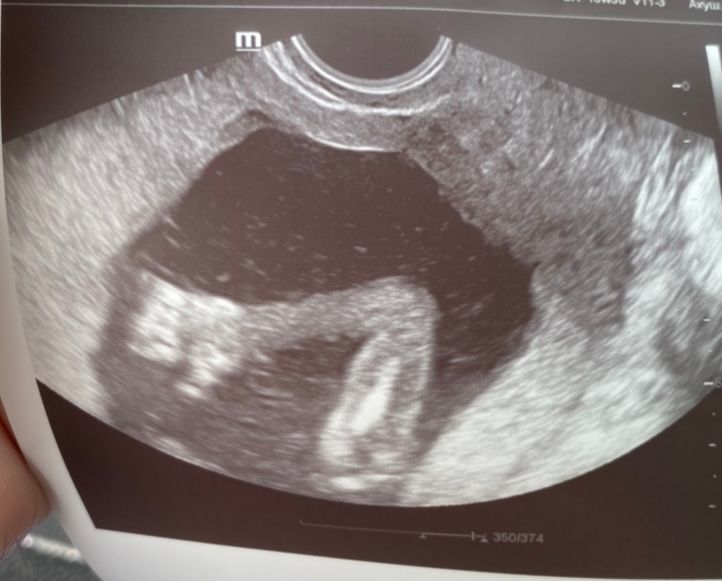

2 дня назад прошли 2 скрининг , все у нас хорошо ☺️Срок по всем узи на неделю больше 🙈в гос учреждениях в заключении пишут срок по М, в платке пишут срок по узи🤷♀️ в общем прям не знаю какой реально срок 😁

Малышок сидит на попке)) брыкается ножками в самый низ 🙈иногда меняет своё положение и чувствую его ножки чуть ниже пупка)

мой сладкий мальчик 🥰весит уже аж 330гр☺️

и вот такой пламенный привет , от моего сладенького 💙